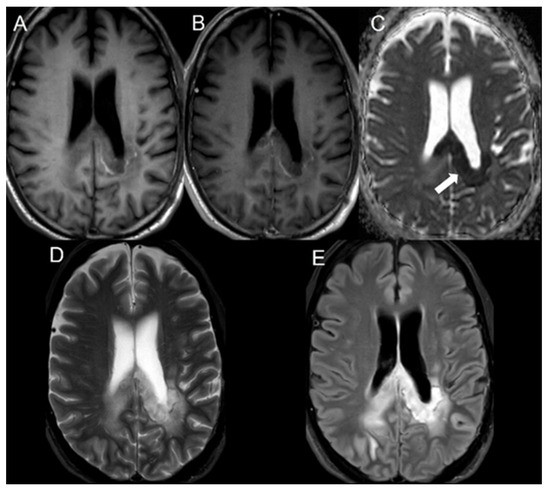

| 1 | Still alive | GBM | + | + | + | CC | N/A | 181 | N/A |

| 2 | 32 | GBM | + | + | + | CC | 90 | 74 | 16 |

| 3 | 45 | GBM | + | + | + | CC | 574 | 61 | 513 |

| 4 | 77 | GBM | + | + | + | CR | 424 | 58 | 366 |

| 5 | 57 | GBM | + | + | + | CC | 647 | 339 | 308 |

| 6 | Still alive | GBM | + | + | + | CC | N/A | 258 | N/A |

| 7 | 48 | GBM | + | + | + | PV | 283 | 16 | 267 |

| 8 | 68 | GBM | + | + | + | CR | 92 | 34 | 58 |

| 9 | 67 | GBM | + | + | + | CR | 573 | 150 | 423 |

| 10 | 64 | GBM | + | + | + | PV | 589 | 25 | 564 |

| 11 | 57 | GBM | + | + | + | CC | 281 | 57 | 224 |

| 12 | 67 | GBM | + | + | + | CC | 75 | 41 | 34 |

| 13 | 65 | GBM | + | + | + | PV | 272 | 90 | 182 |

| 14 | 48 | GBM | + | + | + | PV | 717 | 371 | 346 |

| 15 | 51 | GBM | + | + | + | CC | 229 | 41 | 188 |

| 16 | 72 | GBM | + | + | + | PV | 878 | 49 | 829 |

| 17 | 52 | GBM | + | + | + | CC | 575 | 140 | 435 |

| 18 | 54 | GBM | + | + | + | CC | 651 | 355 | 296 |

| 19 | 83 | GBM | + | + | + | PV | 168 | 36 | 132 |

| 20 | 57 | GBM | + | + | + | PV and CC | 359 | 41 | 318 |

| 21 | 47 | GBM | + | + | + | Parasagittal frontal lobe, cingulate gyrus, CC | 295 | 99 | 196 |